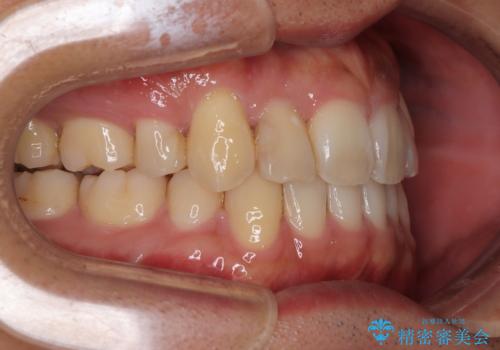

- 「八重歯を治したい」とご相談いただいた患者様の症例をご紹介します。

上下の前歯部に強い叢生(ガタガタの歯並び)があり、そのまま歯を並べると出っ歯になってしまう可能性がありました。

そこで、上下左右の第一小臼歯を抜歯し、歯が並ぶためのスペースを確保し叢生を解消する治療計画を立てました。